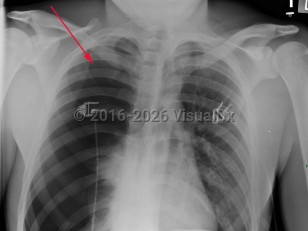

Imaging Studies image of Spontaneous pneumothorax - imageId=3028277. Click to open in gallery.  caption: 'Frontal chest x-ray with a large right pneumothorax with complete collapse of the right lung.'

Frontal chest x-ray with a large right pneumothorax with complete collapse of the right lung.